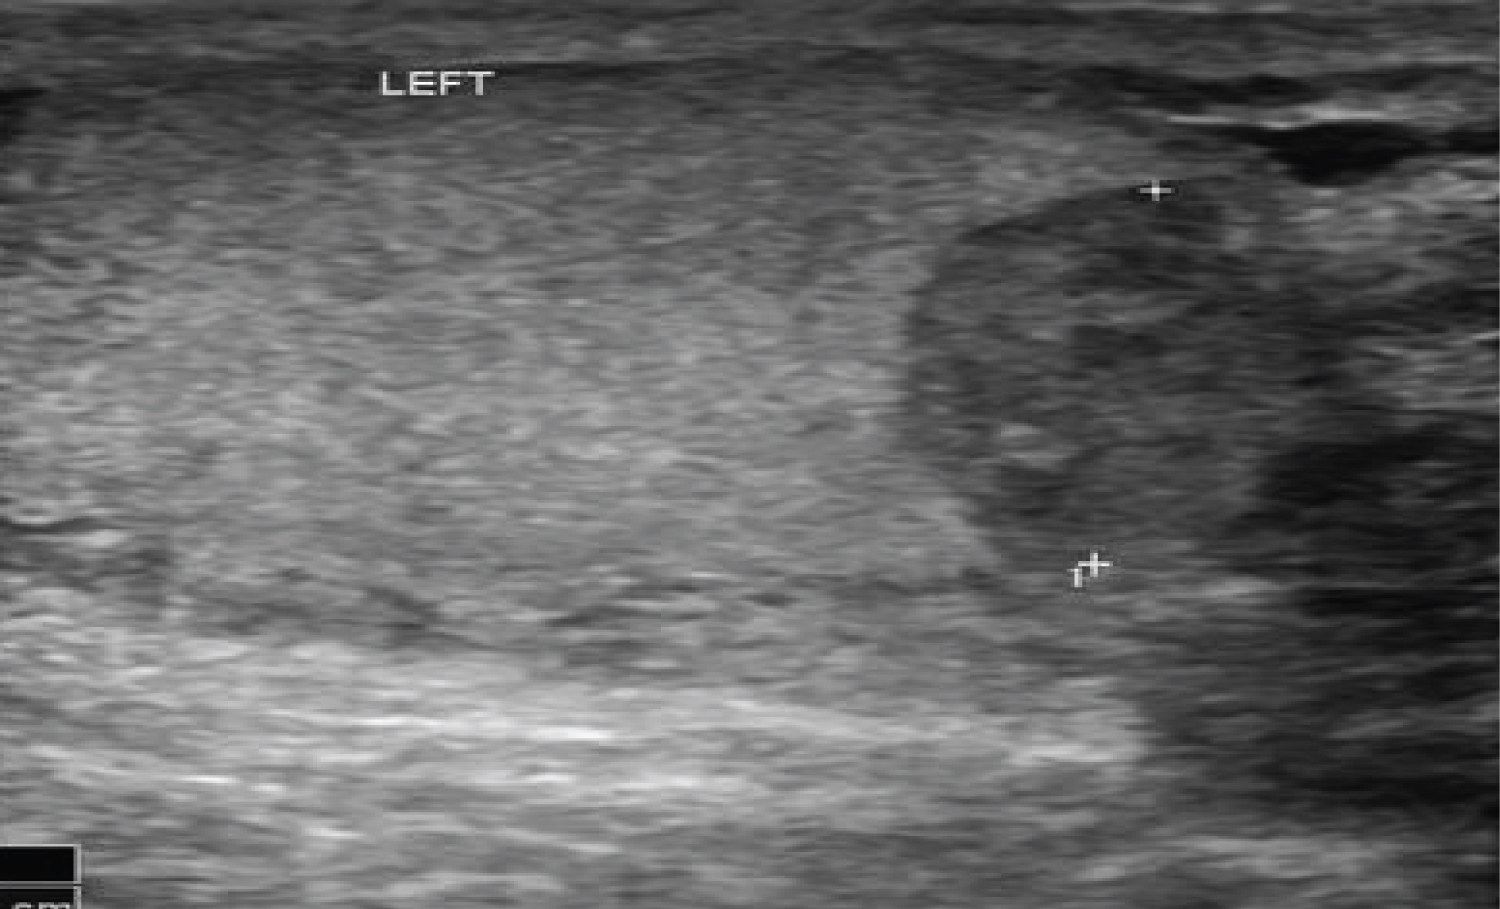

The reset of the clinical examination was normal. An urgent scrotal ultrasound was requested showing ruptured left testicule classified as grade 3 (Figure 2).

Figure 2: Ruptured left testicle. View Figure 2